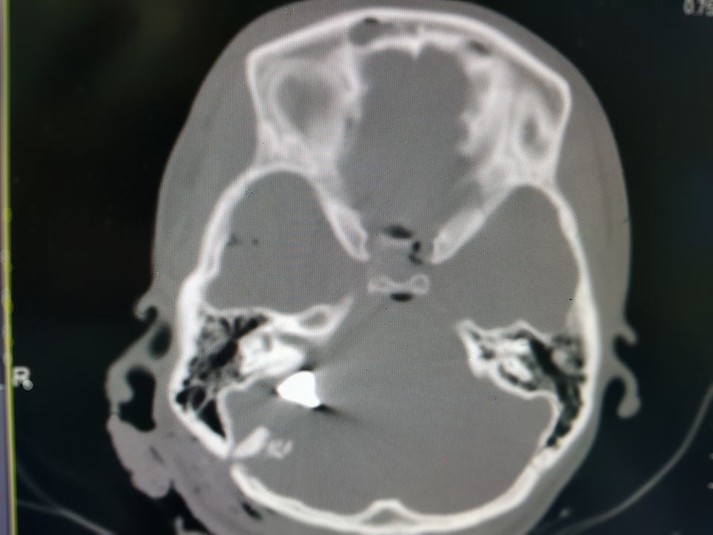

«Вибухова черепно-мозкова травма, перелом кісток склепіння та основи черепа, металеві уламки пошкодили життєво важливі ділянки мозку. Нейрохірурги та анестезіологи понад добу боролися за життя потерпілої, але 23 січня о 9:00 дівчина померла», - повідомив Толубаев.